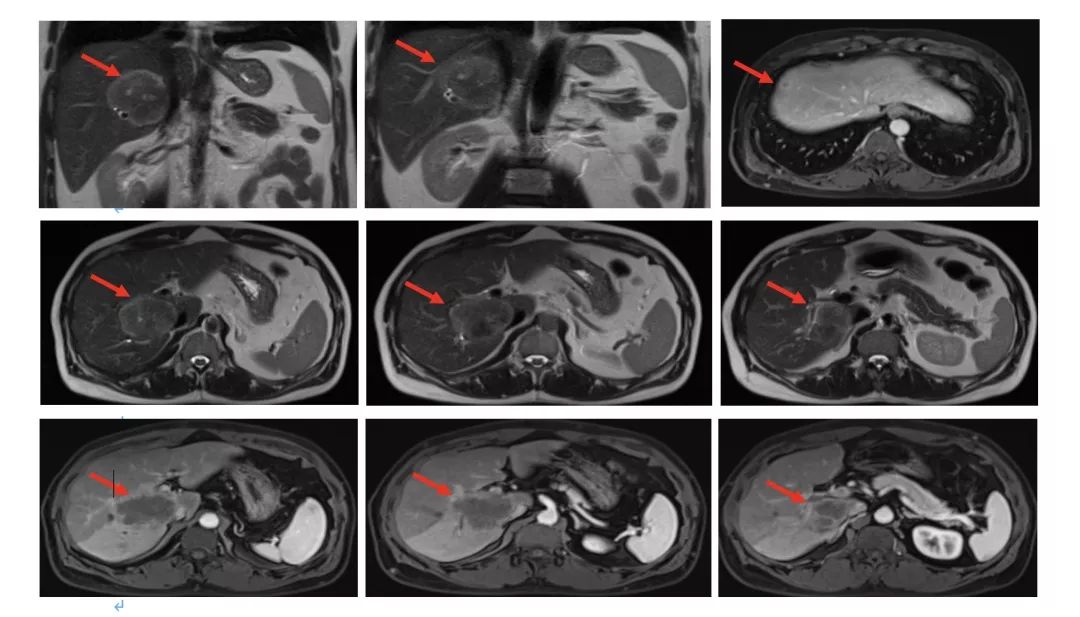

2015.1.22 肝脏MRI:肝右叶后段至尾叶肿块(大小4.9cm*5.9cm*5.4cm),肝右前叶近膈面0.9cm结节影,增强扫描边缘明显强化。

影像学评估 2015.4.7;

4周期评估肿瘤部分缩小;

影像学评估:8周期化疗后,肝脏病灶缩小43%,疗效评价为部分缓解(PR)。

2016.4.28肝脏MRI:治疗后改变。

2017.6复查肝脏再次出现新病灶,右后叶包膜下边缘见2.2cm*1.4cm强化结节。